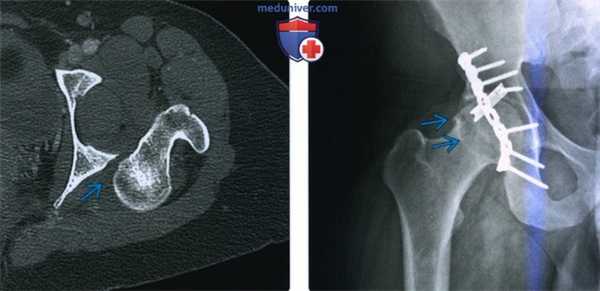

(Слева) КТ в передне-задней проекции, объемная 3D реконструкция: определяется задний вывих головки бедренной кости. КТ выполняется перед закрытой репозицией только если она оказалась неудачной. КТ позволяет оценить положение смещенных осколков, препятствующих репозиции.

(Справа) Рентгенография в передне-задней проекции, выполненная спустя год после заднего вывиха бедра: определяется латеральный подвывих левой головки бедренной кости и нарушение конгруэнтности сустава. Посттравматическая нестабильность бедра является известным, но плохо изученным феноменом.

(Слева) КТ, аксиальный срез: в данном вывихе, репозиция которого возможна только под общей анестезией, визуализируется головка бедренной кости, вколоченная в заднюю губу вертлужной впадины.

(Справа) Рентгенография в передне-задней проекции: у пациента 25 лет, спустя год после заднего вывиха бедра, определяется остеофит, указывающий на ранний остеоартрит. Несмотря на то, что бедро было немедленно подвергнуто репозиции и фиксация перелома задней стенки была полностью анатомически правильная (с помощью длинной реконструктивной пластины и короткой трубчатой пластиной 1/3 длины), повреждение нижележащего хряща быстро привело к остеоартриту.